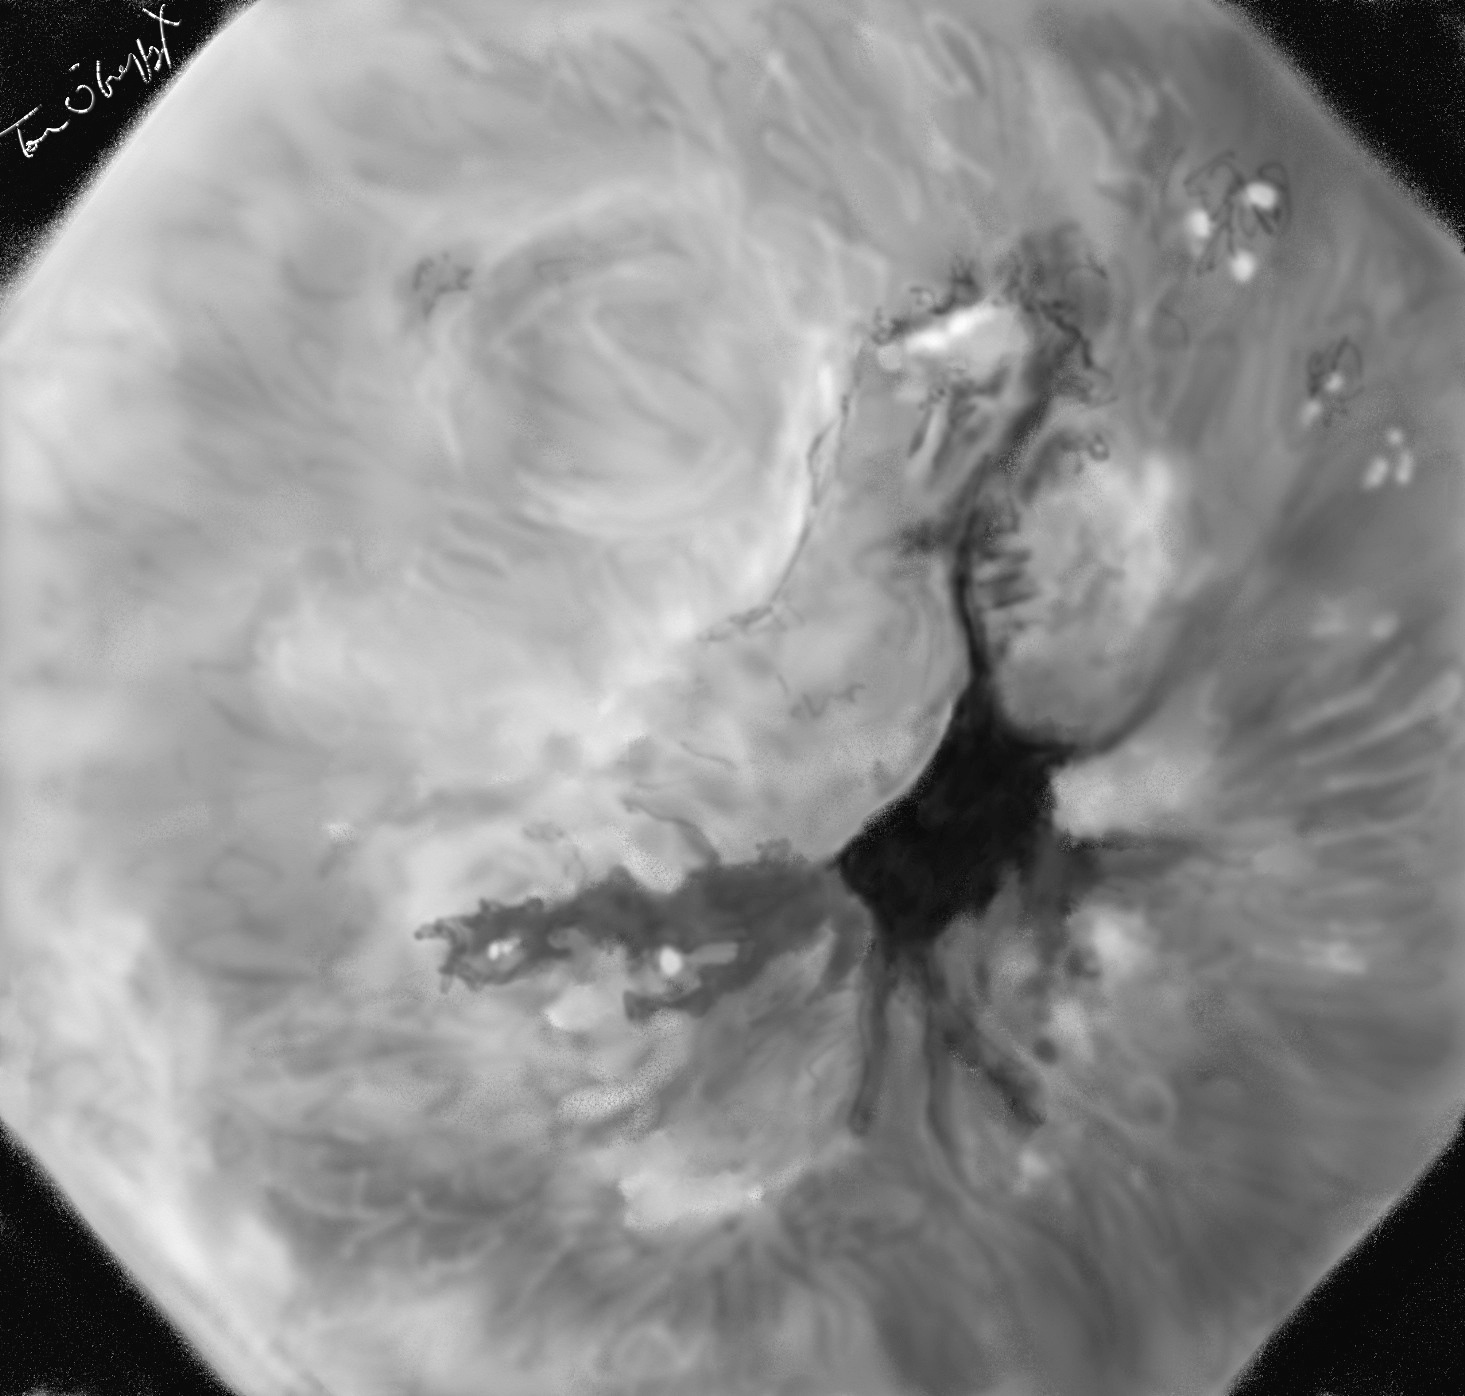

syndrome de mallory weiss, endoscopie digestive haute, ulcérations linéaires longitudinales de la muqueuse à la jonction oesophage-estomac

La prise en charge repose sur la pratique d’une endoscopie digestive haute la plus rapidement possible après stabilisation des fonctions vitales. Celle-ci va visualiser la lésion sous forme d’ulcération unique ou multiples plutôt linéaires à bords nets (de 1 à 2 cm) longitudinales suivant le mouvement de la remontée brutale de l’acide. Ces lésions sont à cheval sur le cardia. Si un vaisseau est à proximité de l’ulcération, un saignement en nappe ou en jet est visualisable, de même que la présence d’un caillot masquant la lésion.